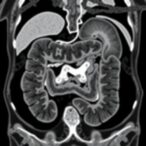

One of the pivotal achievements of this study lies in leveraging exome sequencing of affected individuals, enabling the detection of rare, damaging mutations within protein-coding regions. By filtering through thousands of variants, the researchers pinpointed novel mutations with strong pathogenic potential. These results were further corroborated by functional analyses, which validated gene candidates implicated in nephrogenesis. This robust methodological framework elevates the reliability of their findings, positioning genetic screening as an indispensable tool in clinical nephrology.

Furthermore, the integrative approach combined exome data with detailed phenotypic assessments, enabling the prioritization of candidate variants within clinical diagnostic workflows. This systematic strategy ensures that genetic findings are directly applicable to patient care. The researchers advocate for the incorporation of exome sequencing into standard fetal anomaly scans and newborn screening protocols, which could revolutionize early detection and therapeutic planning for at-risk populations.